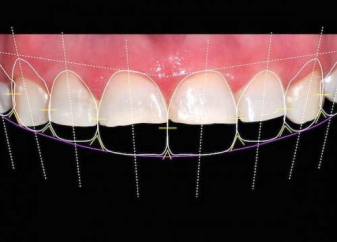

Smile design for the adjacent case

This shows how the gum shaping and 10 porcelain veneers were planned for the previous case. Preplanning allows for you to have input and visualize the final result.